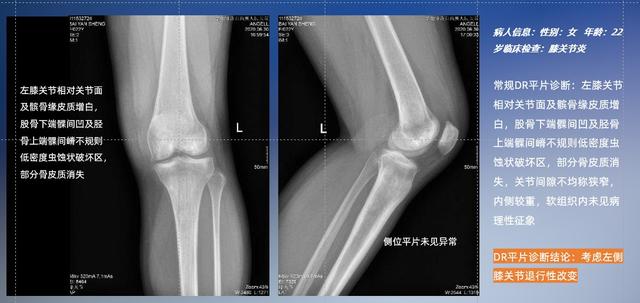

以膝關節疾病檢查為例,膝關節在解剖學意義上是一種較為復雜的最大關節,由脛骨上端、股骨下端及髕骨組成。在股骨與脛骨的關節面之間存在兩塊半月板,分別處于內側、外側。膝關節的運動主要為伸、屈,在半屈位時可進行小幅度的旋外、旋內運動。隨著現代人們體育生活以及肥胖的增加,膝關節疾病出現高發趨勢,特別是關節磨損、膝關節炎與骨關節炎等關節退行性改變,長時間的內翻負荷會造成內側關節軟骨、骨性關節面的磨損。目前針對此類疾病的檢查主要為平片下的負重位檢查、CT檢查以及MRI檢查,相較于非負重位檢查,負重位檢查能更加真實反映膝關節結構中脛骨、股骨、髕骨實際對位關系和關節面的形態特征及關節間隙大小,對膝關節骨關節病診斷準確率高。

普通平片掃描與WR-3D掃描前后診斷結果對比